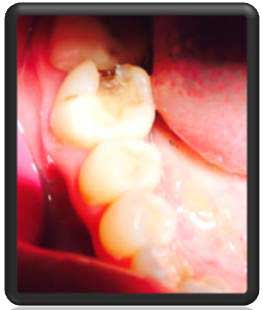

دندان شماره 6 پرکردگی آمالگام(سربی) قدیمی دارد |

پس از بی حسی درمان با حذف پرکردگی قبلی آغاز شد |